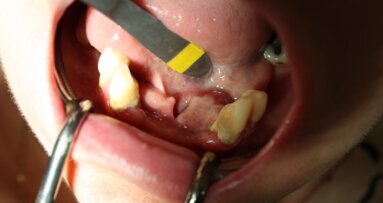

32-letni pacjent zgłosił się do tutejszej poradni chirurgii stomatologicznej celem kontroli po operacyjnym usunięciu w sposób typowy zatrzymanego zęba 48 w położeniu mezjalno-kątowym (Ryc. 1). Ząb został usunięty w innej przychodni ok. 16 dni wcześniej. Po ustąpieniu pozabiegowych objawów towarzyszących, od 5. doby pacjent podawał stopniowo nasilające się dolegliwości bólowe okolicy prawego kąta żuchwy i podżuchwowej, które potęgowały się w czasie spożywania posiłków i mówienia (pacjent stosował dietę miękką wg wcześniejszych zaleceń, zażywał ibuprofen w dawce 2 x 400 mg p.o.). Ponadto pacjent podawał odrętwienie skóry okolicy kąta ust i wargi dolnej po stronie prawej.

W badaniu fizykalnym stwierdzono tkliwość palpacyjną okolicy 48, niewielkie zapalenie otaczającej błony śluzowej oraz niewielką, jednak wyczuwalną ruchomość patologiczną w okolicy kąta po stronie prawej, z nasilaniem się bólu w trakcie badania ruchomości, ponadto dodatni objaw Vincenta po stronie prawej. Wykonane zdjęcie rtg pantomograficzne wykazało szczelinę złamania w okolicy 48, najprawdopodobniej powstałą podczas usuwania zęba zatrzymanego. Jest również prawdopodobne, iż korzystny przebieg linii złamania i niejako „zakleszczenie” odłamów oraz brak wyczuwalnego klinicznie ich przemieszczenia w postaci prawidłowego zgryzu zmniejszyły ryzyko rozwinięcia się ostrego zakażenia miejscowego (Ryc. 2).